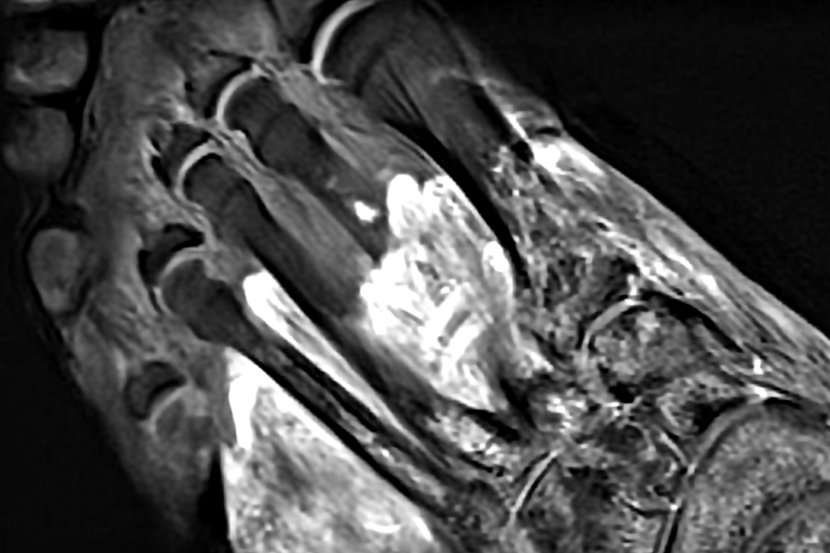

Ultrazvuk, rendgen, MRI i CT skeniranje mogu da otkriju dugotrajno oštećenje koje covid 19 ostavlja na mišićima, živcima, zglobovima, kostima i drugim mekim tkivima pacijenta

Razne vrste medicinskih snimanja, uključujući ultrazvuk, rendgen, MRI i CT skeniranje, mogu da otkriju dugotrajno oštećenje koje covid 19 ostavlja na mišićima, živcima, zglobovima, kostima i drugim mekim tkivima pacijenta, odnosno mogu da potvrde kako telo samo sebe napada. Ovi snimci, prema novoj medicinskoj studiji Northwestern University, objavljenoj u časopisu Skeletal Radiology, mogu da dovedu do boljeg vođenja procesa lečenja obolelih.

- Ono što smo otkrili je da kod nekih pacijenata sa covid 19 pokreće autoimunu reakciju. Drugim rečima, virus "prevari" telo da se samo napadne - objasnila je dr Swati Deshmukh, autor i docent na Medicinskom fakultetu Northwestern University. Kada telo napadne samo sebe, kako je pokazalo je istraživanje, radiološke slike, neke koje koriste kontrast, mogu da pokažu upaljene živce ili mrtva tkiva. Takođe, snimci pokazuju da covid 19 može da traje nekoliko meseci. Kao dokaz za ove trvdnje uzet je primer Tajme Hodžić, 31, iz Albani Parka u SAD. Ona se borila protiv covid 19 u junu 2020, ali je njegov uticaj bio dugotrajan, što je kod nje pokrenulo autoimunu bolest nazvanu covid-indukovani psorijatični artritis.

Radiološki snimci najbolji za uspostavljanje dijagnoze

Radiološke slike zahtevaju "oko" stručnjaka kako bi mogle da se rastumače. Doktor Swati Deshmukh proučavala je razne slike drugih pacijenata sa covid 19, uključujući upaljene živce, mrtva i oštećena tkiva, krvne ugruške i oštećene zglobove. Sve u svemu, ti snimci mogu da pomognu lekarima za donošenje medicinskih odluka za svoje pacijente.

- Na osnovu onoga što slika prikazuje, možemo da preporučimo najbolje sledeće korake za dijagnozu i lečenje kroz ovaj dugi put oporavka. Iz tog razloga, radiolozi imaju nadimak "doktori doktora" - istakla je dr Swati Deshmukh.